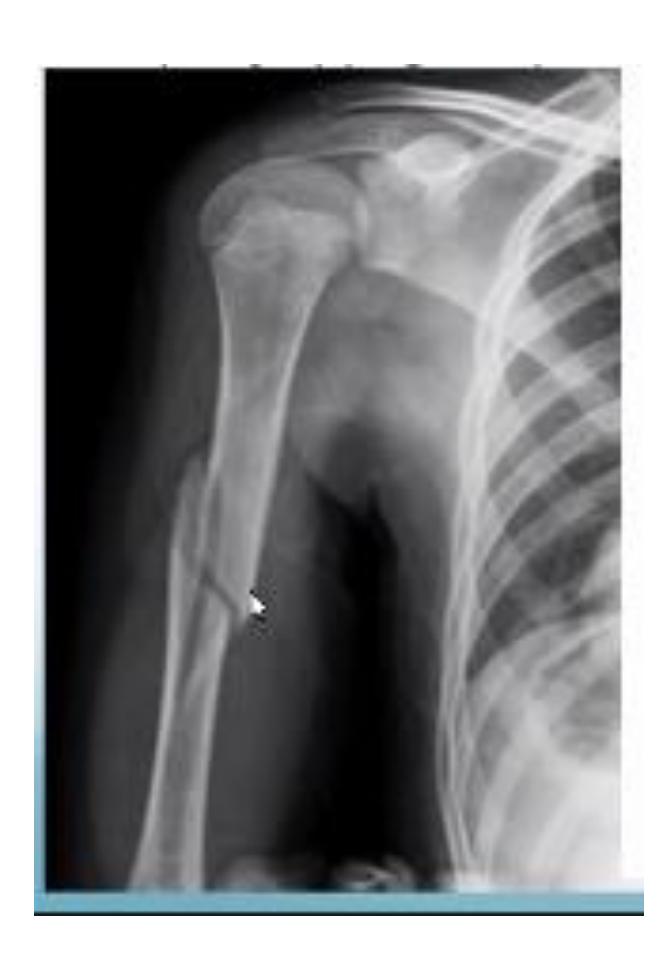

Humeral Shaft Fracture

- Clinical Examination: Check for radial nerve injury by asking the patient to extend the wrist and fingers

What is the associated injury in anterior shoulder dislocation?

- Lesser tuberosity fracture

18-year-old male presented after sport injury and unable to internally rotate his left shoulder. What is the likely finding?